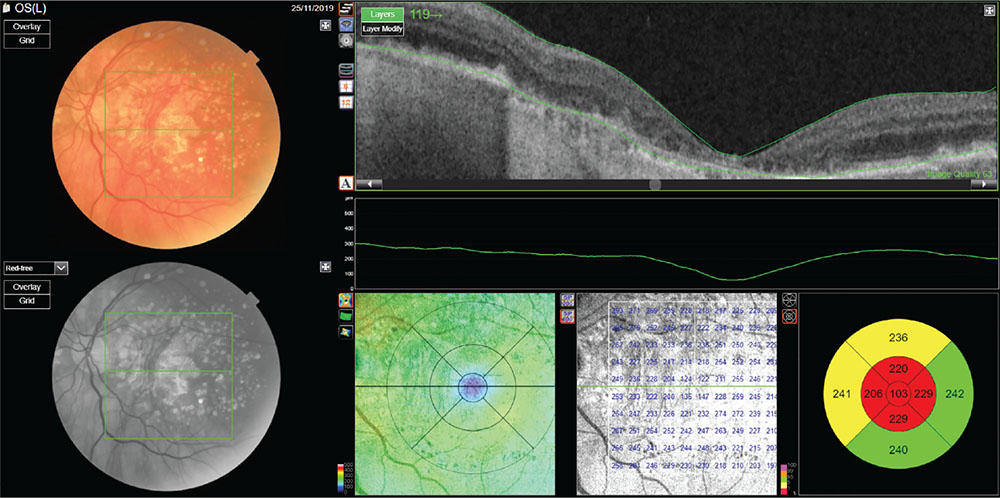

Fig. 1 - Age-related macular degeneration.

Color photograph and optical coherence tomography of an intermediate AMD.